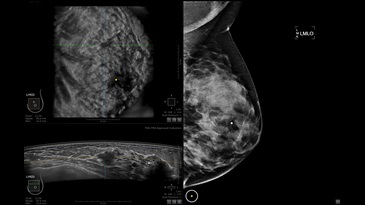

GE INVENIA ABUS – это современный УЗИ аппарат, который создан для точной и эффективной диагностики сканирования с высокой плотностью молочных желез. Выявляемость патологий раковых и предраковых стадий заболевания составляет 55%, что в конечном счете позволяет ставить врачу точные и своевременные диагнозы. Традиционные методы использования маммографии не показывают такой выявляемости, ограничиваясь лишь 3-38%.

• Получение объемных 3D изображений с возможностью покадрового просмотра

• Отображение объемных 3D ультразвуковых изображений, которые состоят из традиционных поперечных и воссозданных коронарных и сагиттальных проекций

• Стандартизованная ориентация изображения: «толстый срез» в коронарной плоскости; поперечная; сагиттальная плоскость; радиальный и антирадиальный поворот изображения; просмотр исключительно области интереса

• Программное обеспечение Invenia ABUS Review Software для рабочей станции